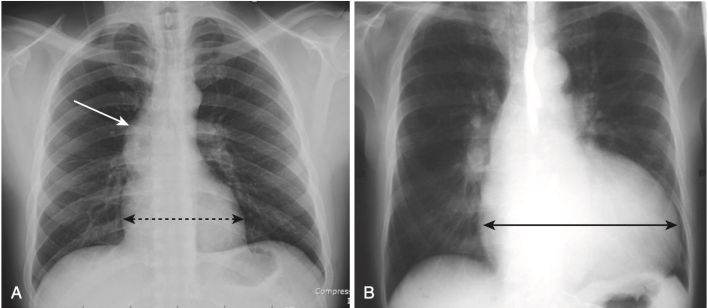

- Chứng tim lớn (Cardiomegaly), khi được nhận ra trên phim X quang ngực, chủ yếu là do giãn lớn của tâm thất, không phải do giãn rộng riêng biệt của tâm nhĩ. Do đó, tim thường có kích thước bình thường trong bệnh hẹp van hai lá sớm, cho dù tâm nhĩ trái đã to ra.

- Nói chung, sự lớn của buồng tim rõ rệt nhất sẽ xảy ra do quá tải thể tích chứ không phải do quá tải áp suất, do đó các buồng tim lớn nhất thường được tạo ra bởi các van bị trào ngược hơn là van bị hẹp. Do đó tim thường sẽ lớn hơn khi có trào ngược động mạch chủ hơn là hẹp eo động mạch chủ, và nhĩ trái thường sẽ lớn hơn khi trào ngược van hai lá so với hẹp van hai lá (Hình 4).